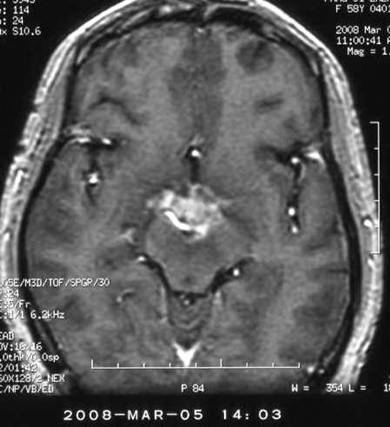

天幕脑膜瘤:

治疗前

治疗后

脑干胶质瘤:

视交叉胶质瘤: